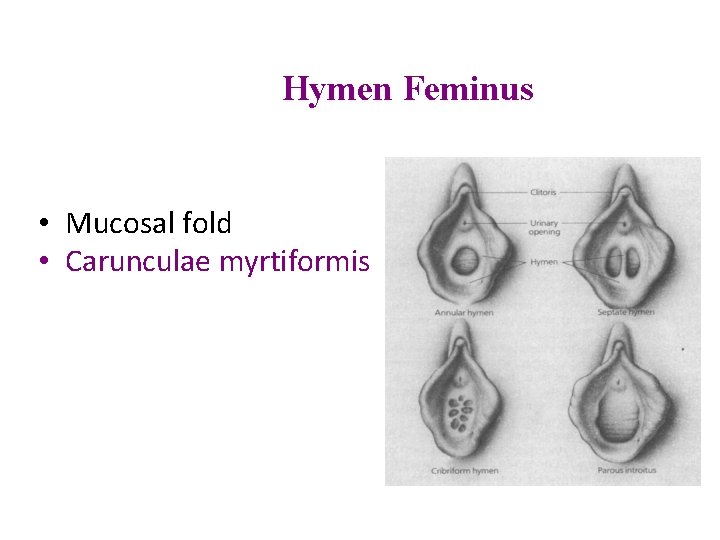

Hymen Feminus • Mucosal fold • Carunculae myrtiformis